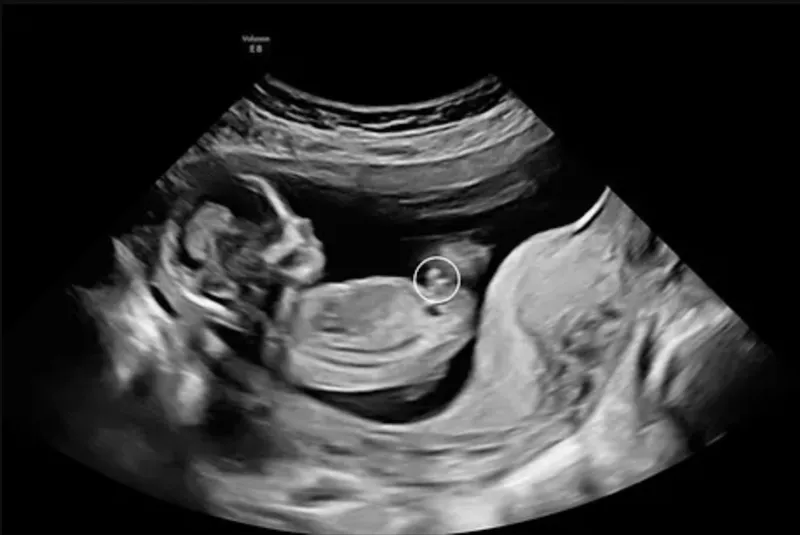

Tidlig scanning som også er kaldet for tidlig graviditetsscanning, kan vi udføres fra uge 5+0, og er en af de første undersøgelser, som gravide vælger for at bekræfte graviditeten og få en præcis vurdering af fostrets udvikling. Med tidlig scanning hos A-scan, bekræfter vi hjerteblink, fastlægger antallet af fostre og beregner en præcis terminsdato. Denne graviditetsscanning er afgørende for at sikre, at din graviditet forløber som forventet, og at alt udvikler sig normalt.

Hos os kan du få tidlig scanning allerede fra uge 5+0. For det mest præcise resultat anbefaler vi scanning fra uge 6+3. Start din graviditet med vished – ro og tryghed.